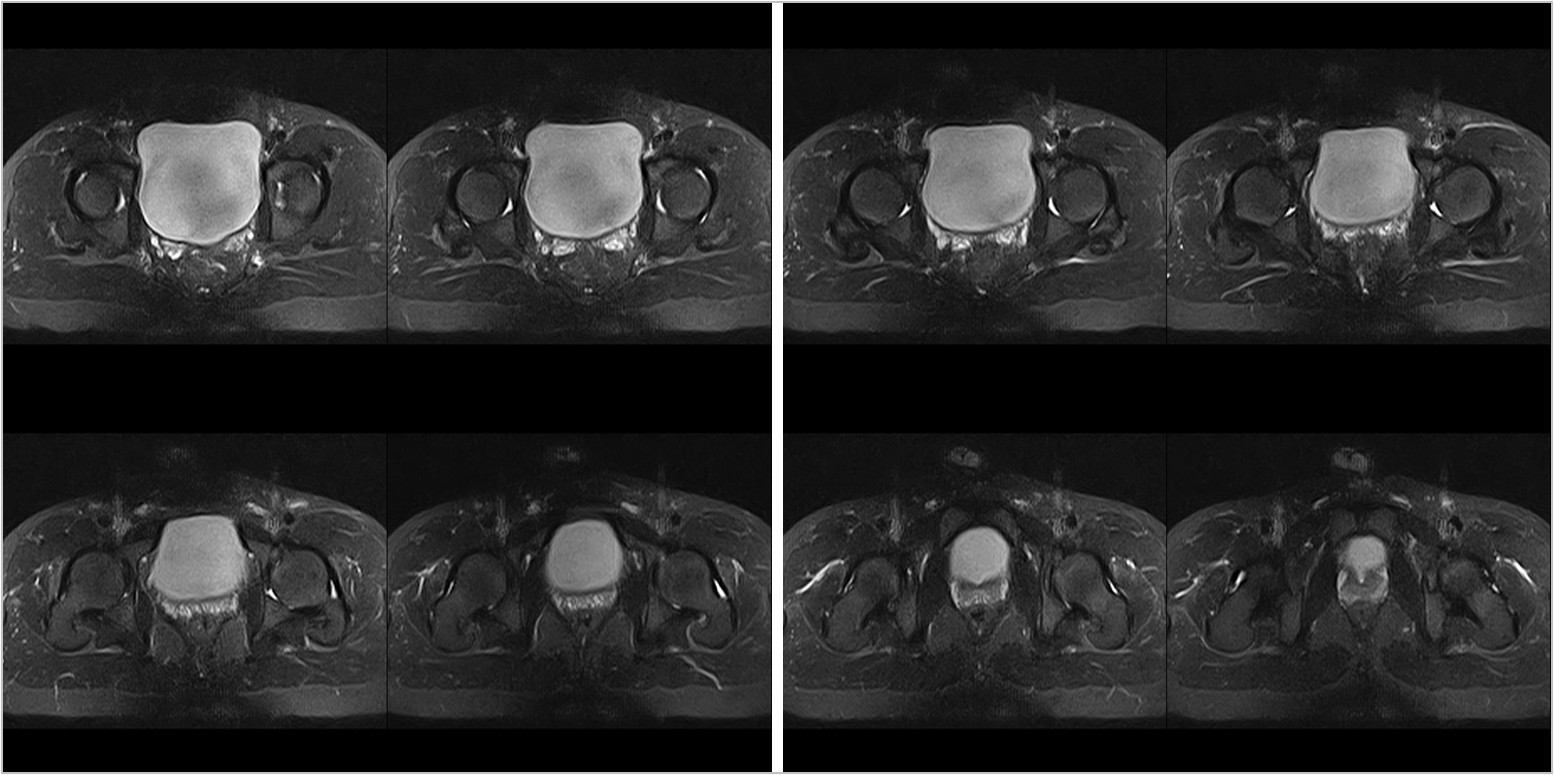

Hình ảnh lâm sàng